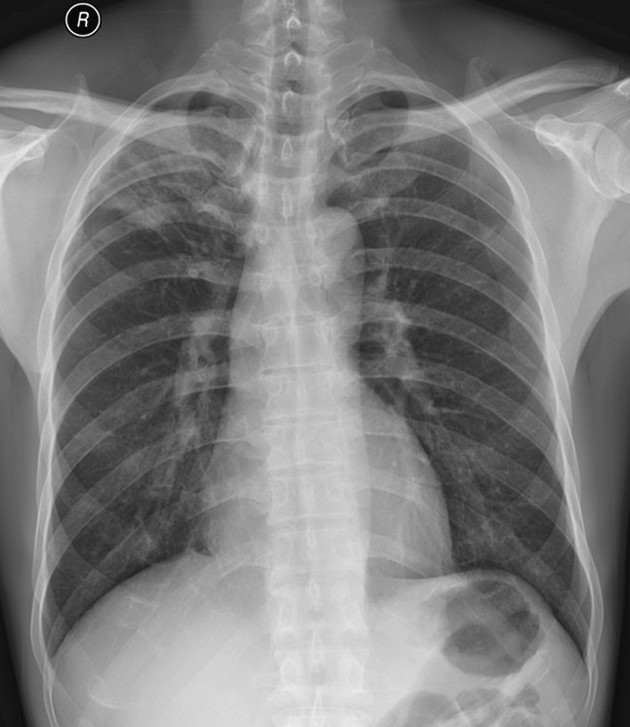

图(三)、继续抗结核治疗一个多月后复查的正位胸片: